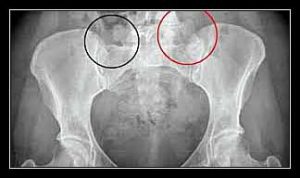

Chụp X-quang: hình trên phim X-quang thường biểu hiện rất muộn cho nên trong những trường hợp nghi vấn chụp citi xương giúp ích cho chẩn đoán.

- VIÊM CỨNG KHỚP SỐNG; thường nhất là viêm khớp cùng – chậu hai bên; đàn ông trẻ; kháng nguyên HLA B27.